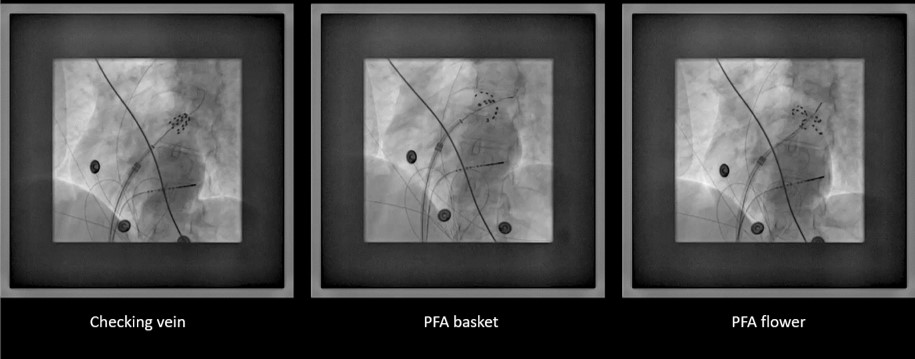

Esta nueva tecnología permite hacer ablación de fibrilación auricular de forma más rápida y con menos riesgos para el paciente. El hospital Ramón y Cajal ha sido uno de los 3 centros pioneros en España en su uso, con excelentes resultados.